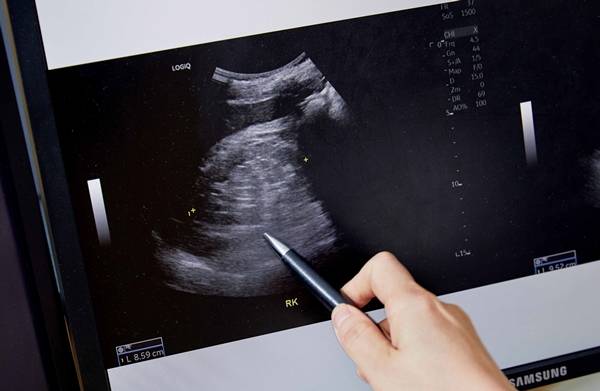

콩팥 손상의 증거는 혈뇨, 단백뇨와 같은 소변 검사로 쉽게 확인할 수 있다. 콩팥 기능은 혈액 내 크레아티닌 수치를 체크하면 된다. 따라서 정기적으로 소변 검사와 혈액 검사를 받는 것이 중요하다. 특히 당뇨병이나 고혈압과 같은 고위험군 환자들은 1년에 1회, 보통 6개월에 한 번 정도 콩팥 검진을 받는 것이 권장된다.